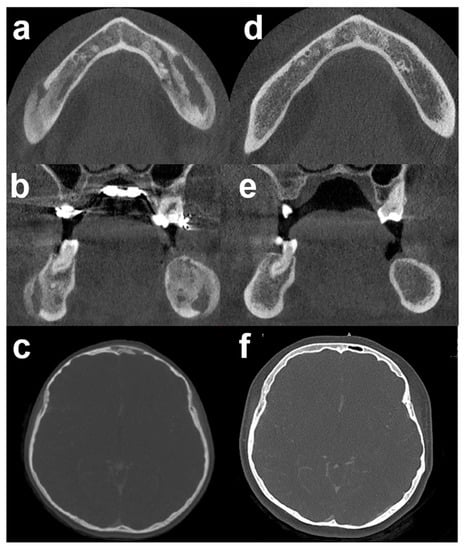

Based on these findings, a final diagnosis of chronic bacterial osteomyelitis was established. We initiated a 6-month course of oral antibiotic treatment with levofloxacin (500 mg, once a day) and cotrimoxazole (= trimethoprim/sulfamethoxazole, TMP/SMX) (400 mg/80 mg, two times a day). Periodic blood tests and renal function monitoring were performed with normal results. At 3 months, the patient was symptom-free. At 6 months, CBCT/CT scans showed a normal bone structure (Figure 4). At 2 years post-antibiotic treatment, no clinical or radiological relapse had been noted.

Figure 4. 3D computed tomography before and after antibiotic therapy: (ac) CBCT/CT scan before antibiotic therapy. (df) The corresponding CBCT/CT scan, 6 months after antibiotic therapy demonstrated complete bone healing. Bone sclerosis and osteolysis (mixt pattern) disappeared in mandible (d,e) and frontal bone (f). CBCT: Cone Beam Computed Tomography.